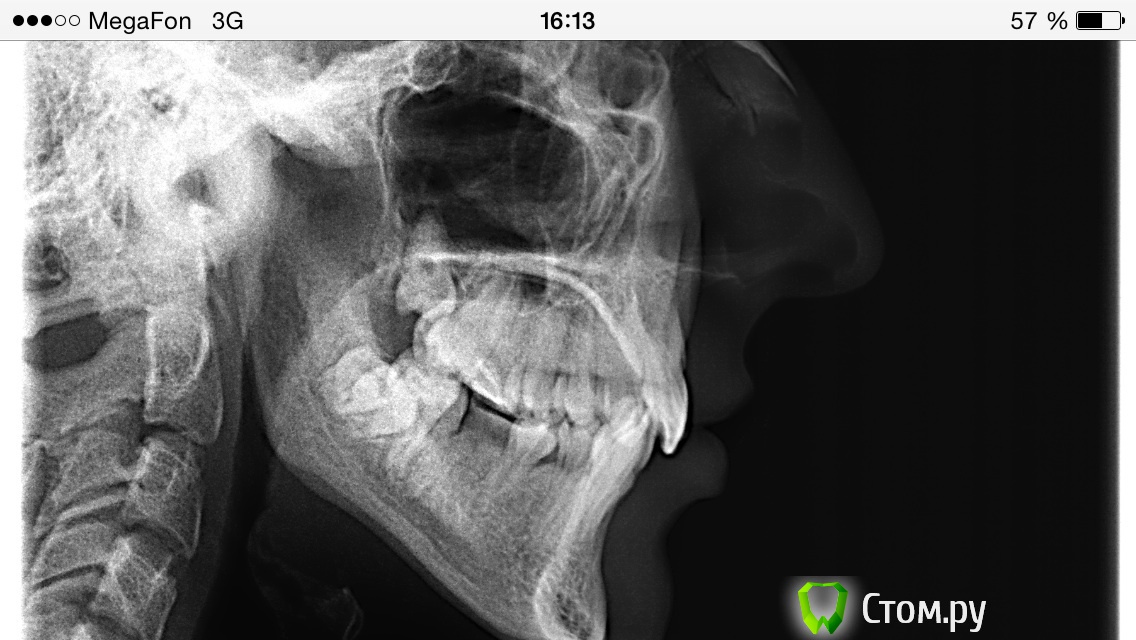

innessa Опубликовано 24 апреля, 2014 Автор Поделиться Опубликовано 24 апреля, 2014 трг и оптг Ссылка на комментарий

m.d.n Опубликовано 25 апреля, 2014 Поделиться Опубликовано 25 апреля, 2014 Поместите ссылку чтобы можно было скачать файл. Надо увидеть не что нибудь а иметь исходный файл снимка вашего чтобы провести его анализ. У вас вертикальный тип роста и как мне кажется верх и низ в ретро положении. Будет снимок скажу больше. Я могу вам порекомендовать только сменить доктора . я ведь вас не вылечу через форум. Ссылка на комментарий